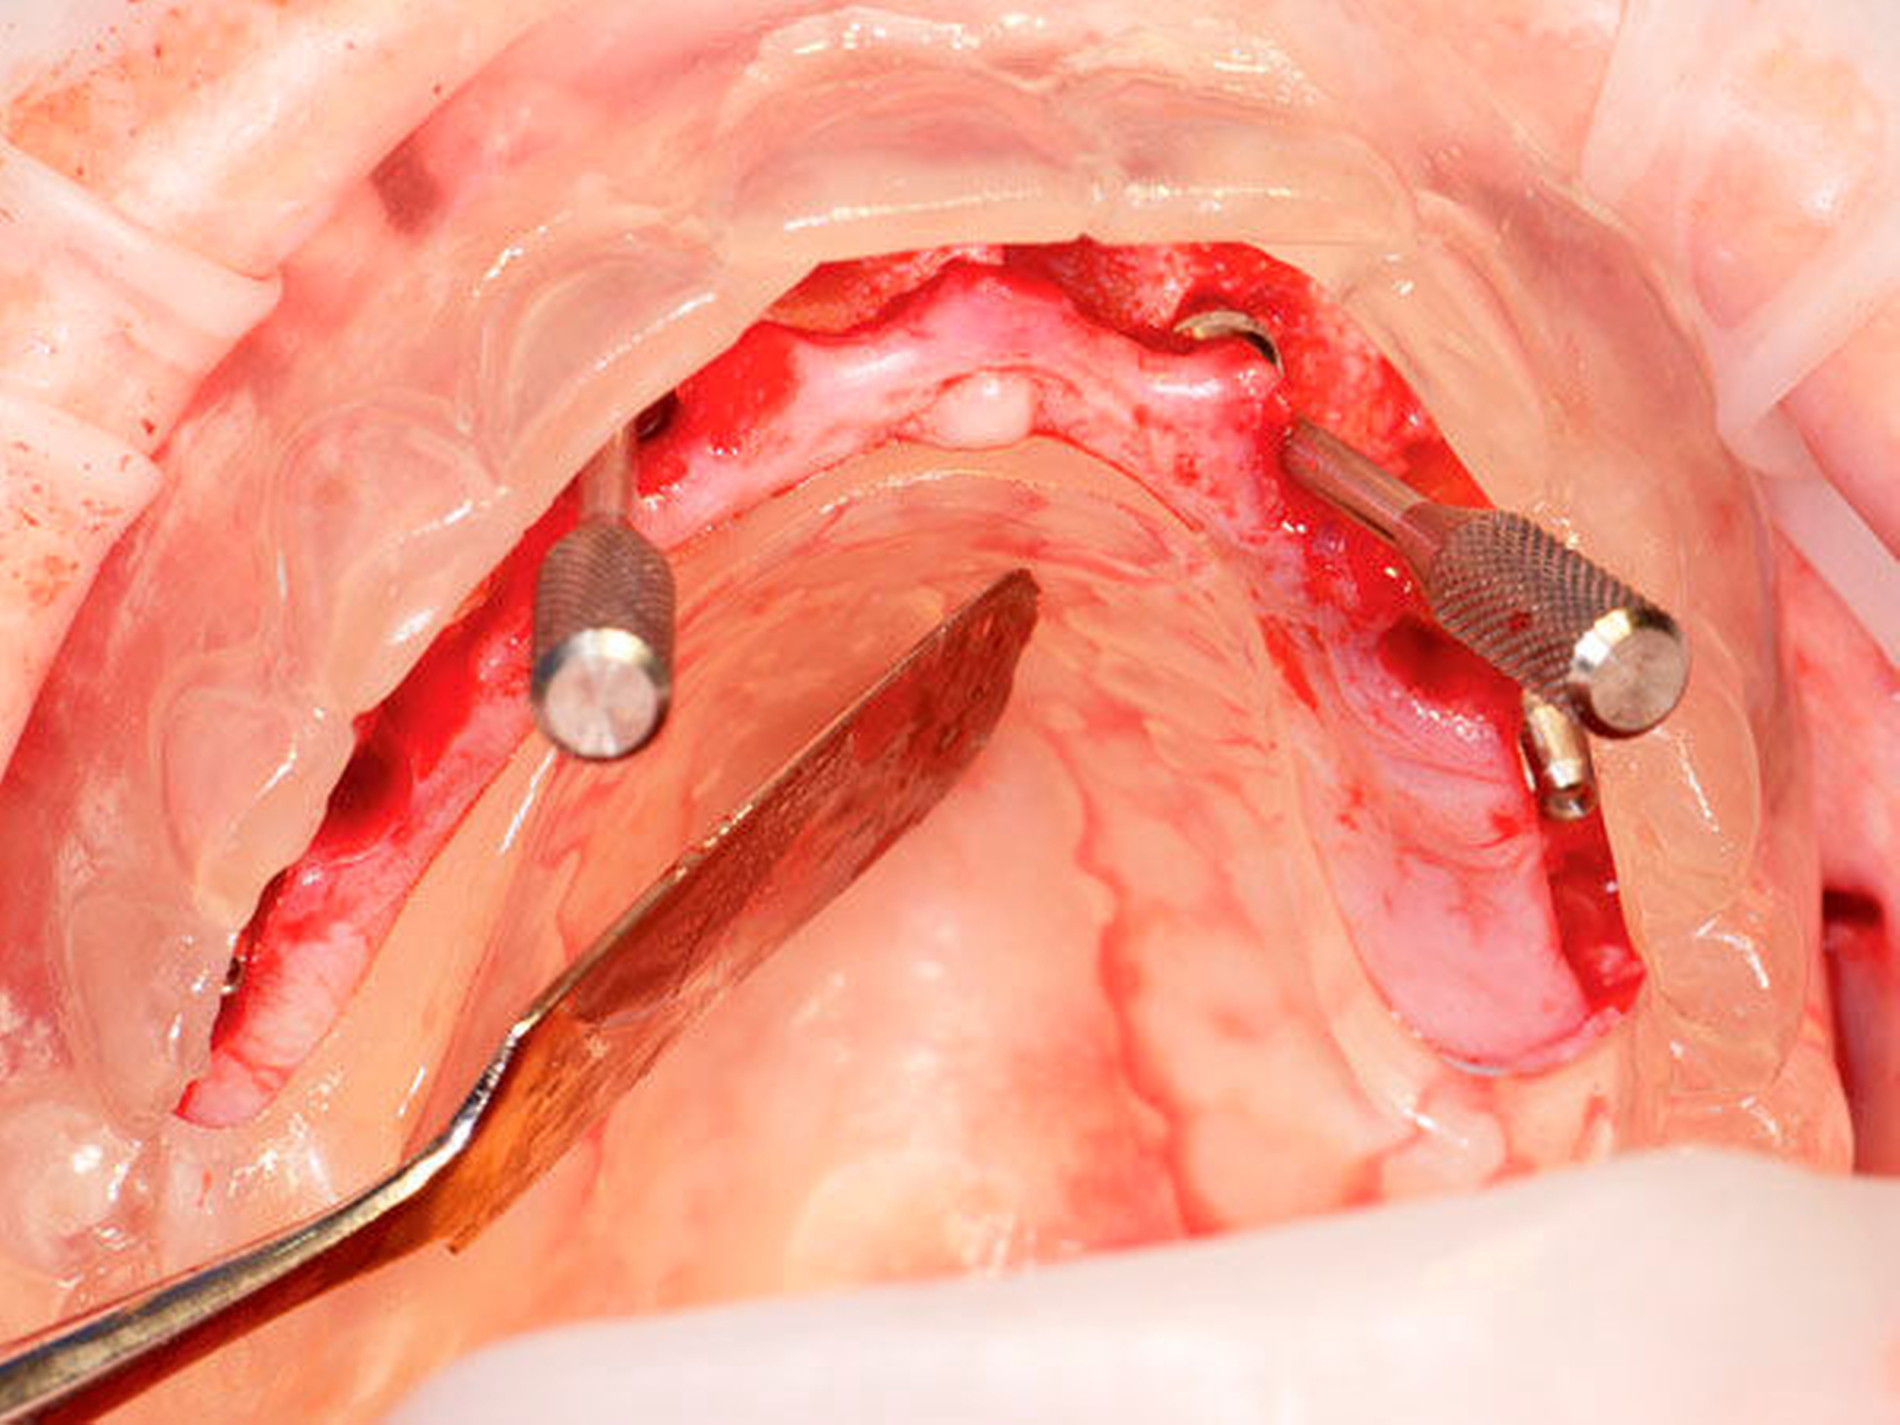

Nach der Darstellung des Kiefers wird im Unterkiefer das Foramen mentale beziehungsweise im Oberkiefer die mesiale Kieferhöhlenwand durch eine kleine Perforation dargestellt. Eine senkrecht zur Gesichtshorizontalen eingebrachte Orientierungsschablone (Abbildung 1) dient bei der Insertion der in einem Winkel von 30° bis 45° angulierten distalen Implantate sowie bei der Positionierung der Abutments als Hilfe. Die Orientierung der vorderen Implantate sowie die Auswahl der Abutments wird mithilfe der im Vorfeld hergestellten Schablone aus transparenten Kunststoff durchgeführt (Abbildung 2), die auch als Schablone für die Bissnahme dient. Die Abutments stehen in verschiedenen Winkelungen zur Verfügung und gleichen die Neigung der Implantate aus. Der durch die Nivellierung des Kiefers gewonnene Knochen kann an anderer Stelle als Aufbau genutzt werden, um eine Kieferform zu erreichen die als Basis für eine hygienefähige festsitzende Versorgung dienen kann. Die Implantation selbst wird jedoch grundsätzlich im ortsständigen Knochen durchgeführt.